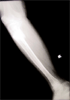

Hypertrophic Non-Union Tibia

Hypertrophic non-union tibia with deformity in 54 years old female

Pre

Op

Xrays